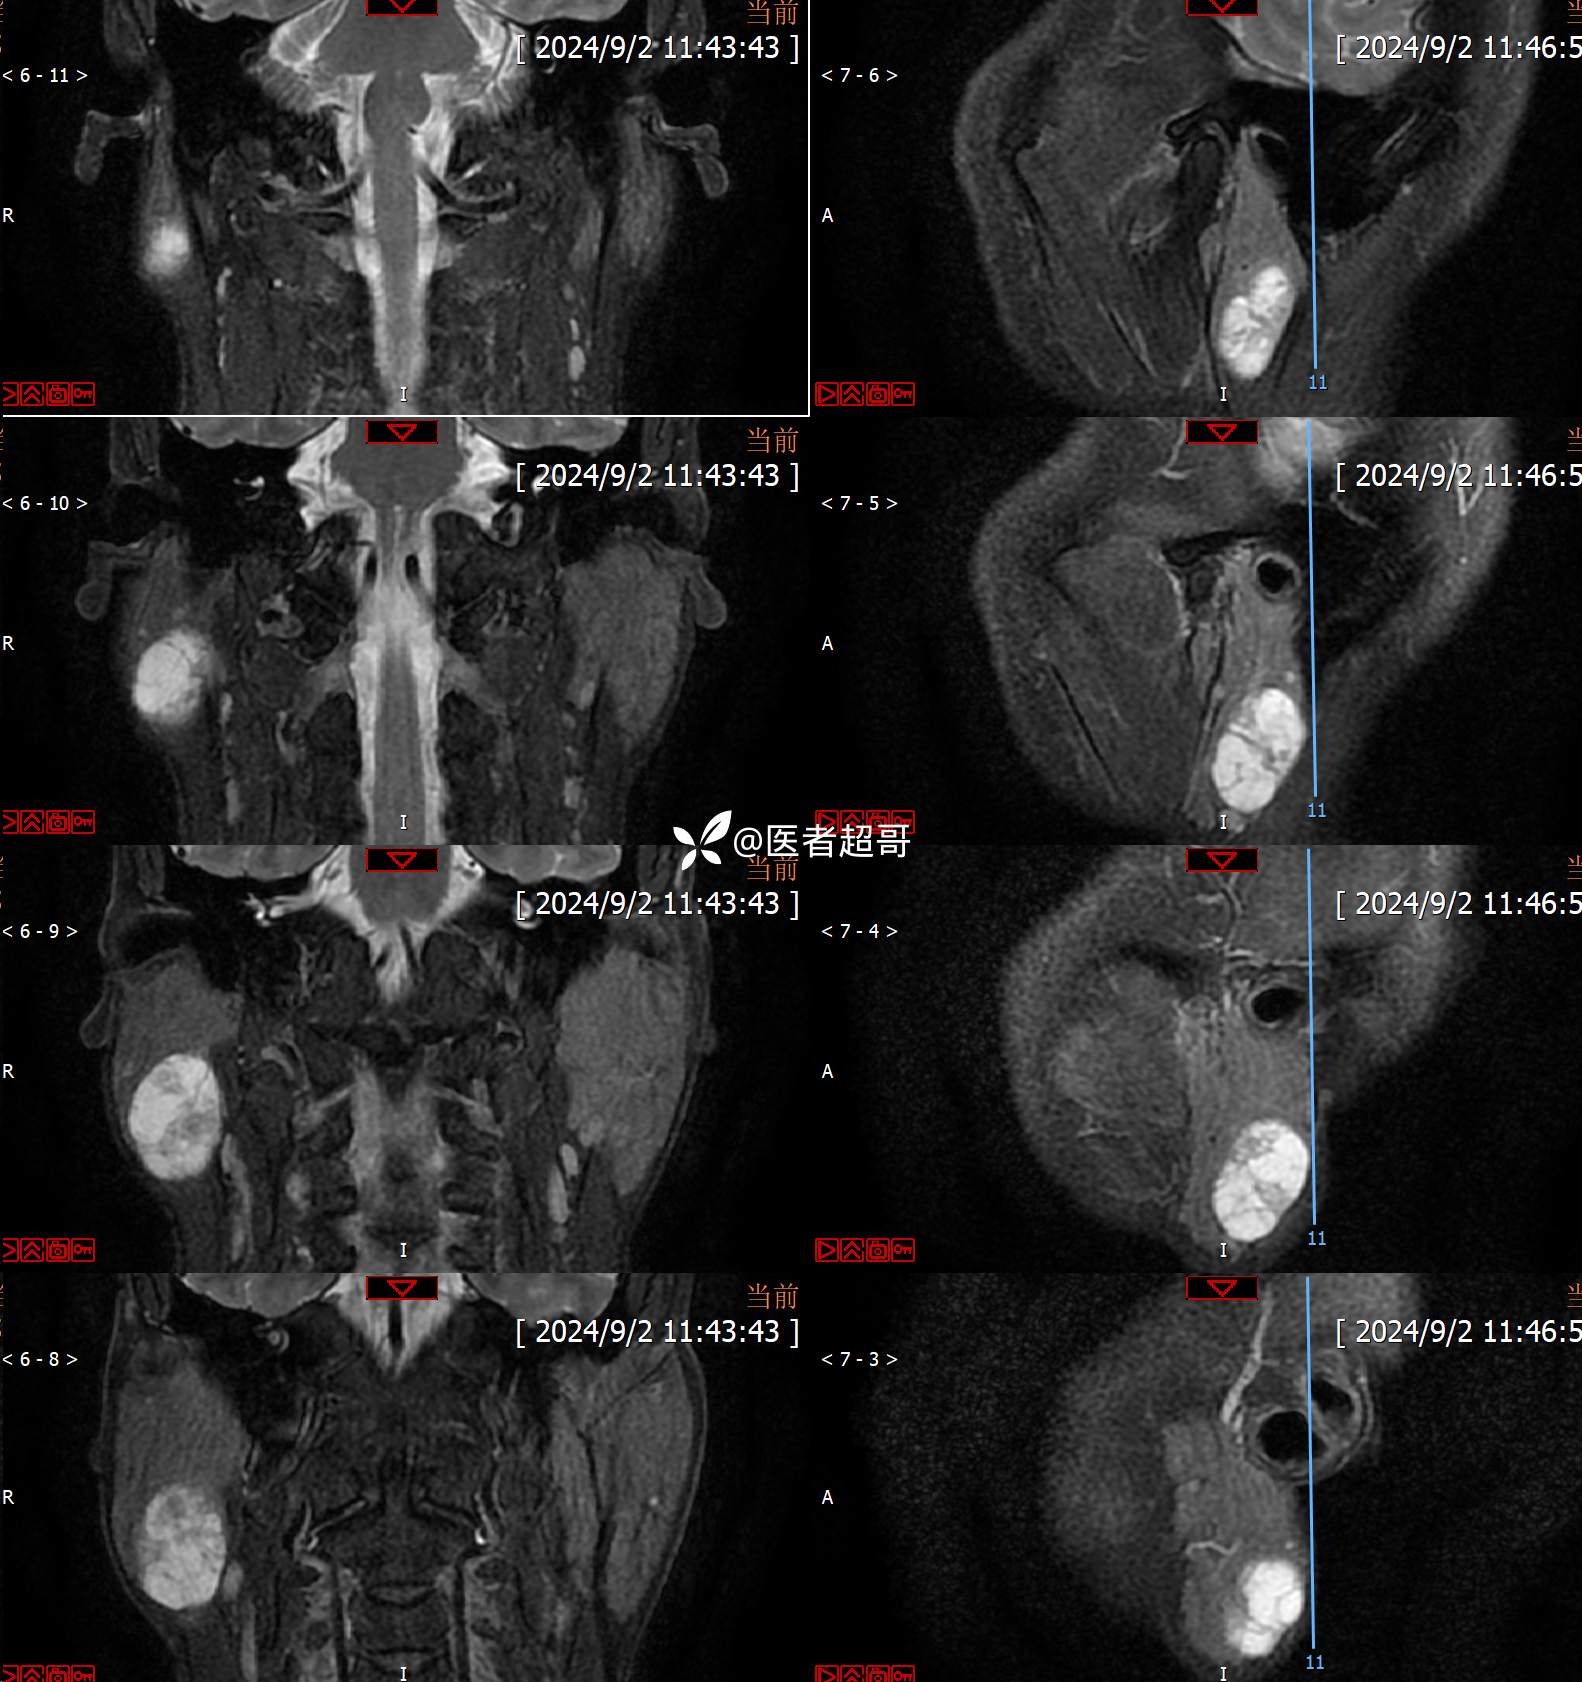

腮腺肿物,CT、MRI齐全,情诊断分析,有详细术程及病理!

主诉:发现右腮腺肿物6个月。

现病史:患者于6个月前无明显诱因发现右侧腮腺区肿物,无疼痛,无局部皮肤破溃,无吞咽困难,无听力下降,无发热,无头痛头晕,患者自发病后在外未治疗,6天前于当地卫生院检查建议手术,为求手术治疗,来我院就诊,门诊以“腮腺肿瘤(右)”收入我院。患者自发病以来,神志清楚,精神可,饮食可,睡眠可,大便正常,小便正常,体重无明显变化。